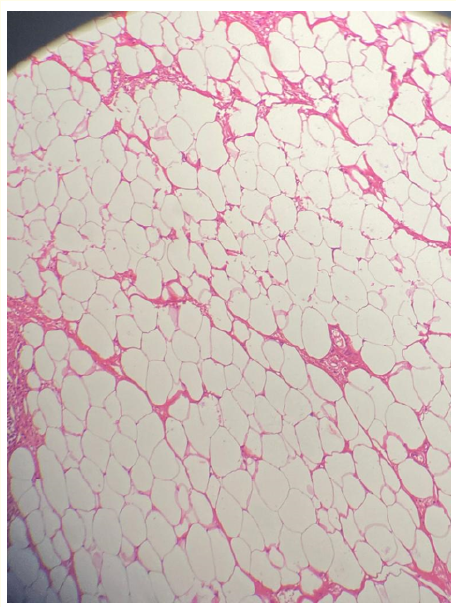

Carpal Tunnel Syndrome Caused by a Lipoma of Chance Discovery: A Case Report

Amine EL Maqrout, Mohamed Jalal EL Mekkaoui, Moncef Boufettal, Rida-allah Bassir, Mohamed Kharmaz, Fouad Zouaidia, Moulay Omar Lamrani and Mohamed Saleh Berrada. 6(4): 106-112.